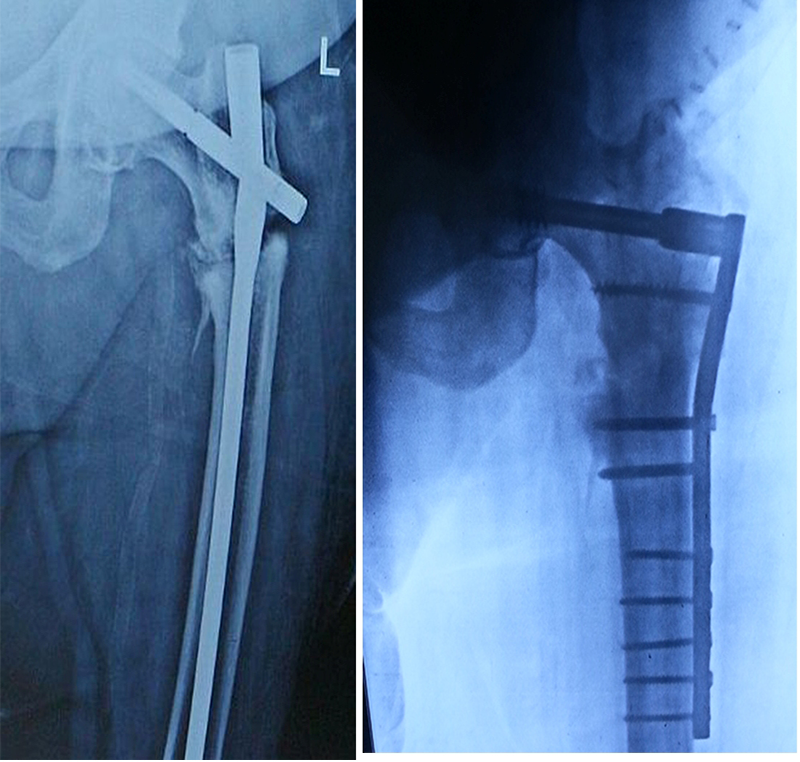

Pre-Operation And Post-Operation X-RAY

Femur Fracture